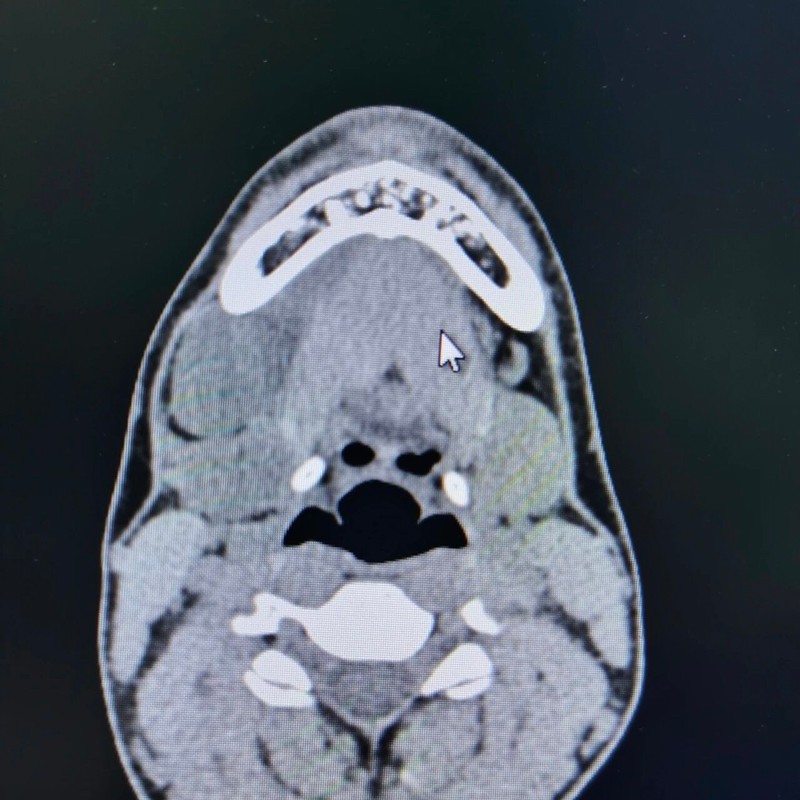

近日,来凤县人民医院耳鼻喉头颈外科成功为一名颌下腺源性囊肿患者实施了小切口内镜辅助下颈部肿物切除术。该手术由湖北民族大学附属民大医院下派专家,现任来凤县人民医院副院长、耳鼻喉科主任李良波教授主刀,手术过程微创精准、安全顺利。这一技术的开展,标志着该院在颈部微创外科诊疗领域取得了新的突破。

为兼顾治疗效果与患者对美观的需求,李良波教授与科室团队进行了周密评估,精心设计了个性化手术方案,决定采用“小切口+内镜辅助”的微创术式。术中,借助高清内镜系统,手术视野清晰,解剖层次精准。医生在微小的切口下精细操作,不仅完整剥离并切除了颌下腺源性囊肿,确保了无残留,还最大限度地保护了颈部的正常组织与外观。